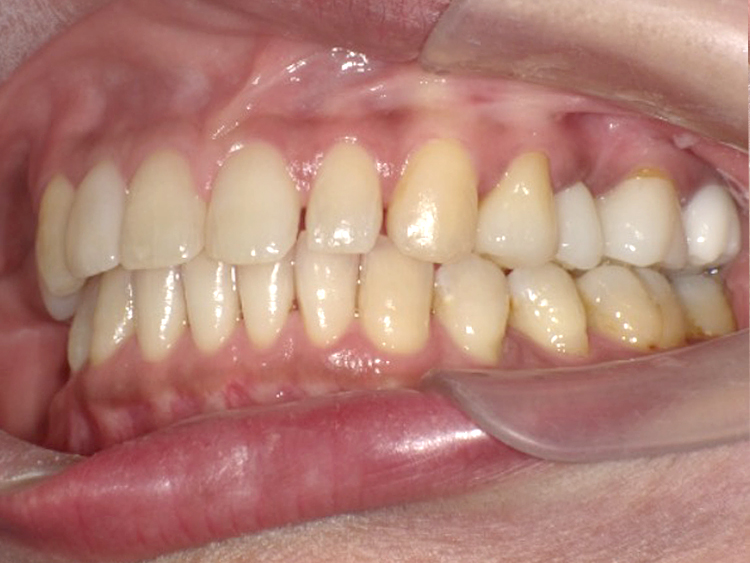

症例6

Before

After

| 主訴 | 噛み合わせが気になる |

|---|---|

| 年齢 | --- |

| 治療 期間 |

約2年11ヶ月 |

| 治療 内容 |

インビザラインコンプリヘンシブ 右上6番・左上6番ALLセラミッククラウン |

| 治療費 | ¥1,116,000(税込)/調整料含む |

| 治療のリスク | 歯を動かすことで、歯茎が下がるリスクある。 矯正終了後は、リテーナーを使用し、後戻りを防ぐ必要がある。 |